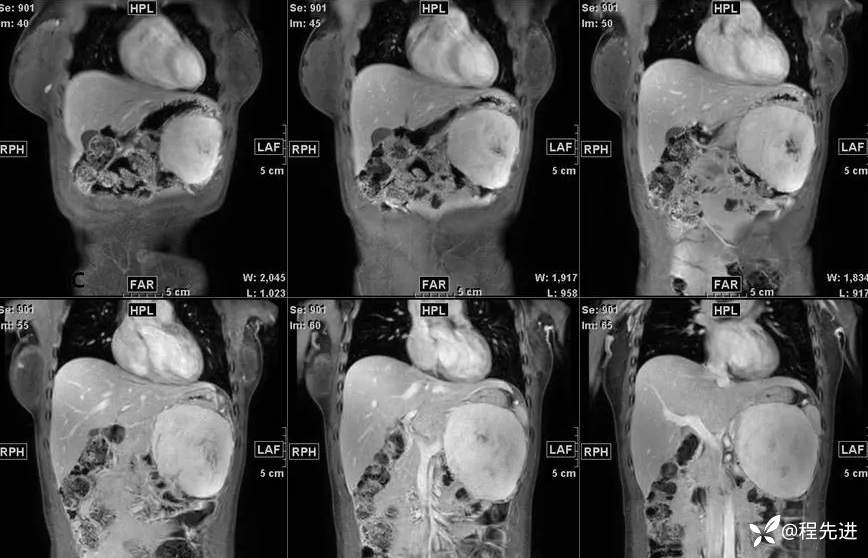

影像检查:

T1: